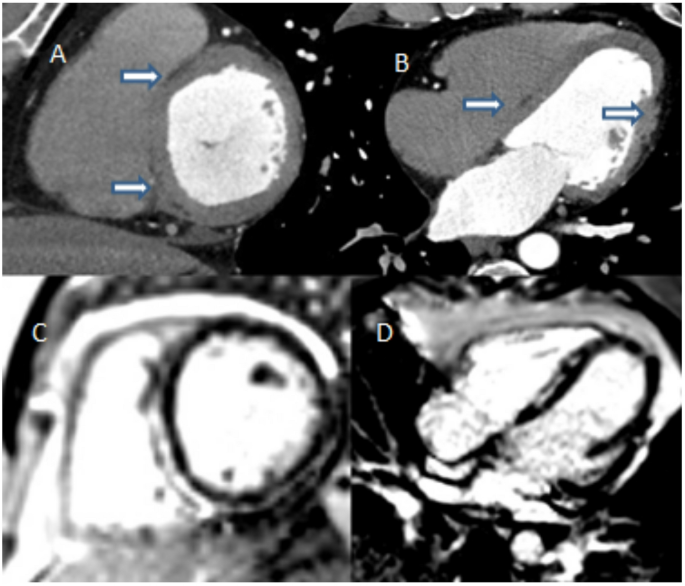

一名52岁的男性,超声心动图显示其射血分数略有下降,因此接受了冠状动脉造影(CCT)以评估是否存在冠状动脉疾病。CCT结果显示冠状动脉正常,但在心内膜间室间隔和心外膜顶端区域的侧壁上发现了低密度区(脂肪纤维化)(见图1A–B)。鉴于CCT的结果提示可能患有心肌病,为明确病因,进一步进行了心脏磁共振成像(CMR),结果显示心内膜间室间隔以及心外膜下侧和前壁存在环状晚钆增强(LGE)现象(见图1C–D),这提示可能为致心律失常性心肌病。基因检测发现filamin-c基因(FLNC)存在致病性变异。该病例表明,CCT除了可用于评估冠状动脉疾病外,还能提供详细的心肌解剖信息。对于无法进行CMR的患者,CCT可作为组织特征分析的替代方法。虽然CCT在软组织分辨率和组织特征分析方面不如CMR,但近年来扫描仪技术和后处理算法的进步提高了其评估心肌纤维化、脂肪浸润和结构异常的能力。